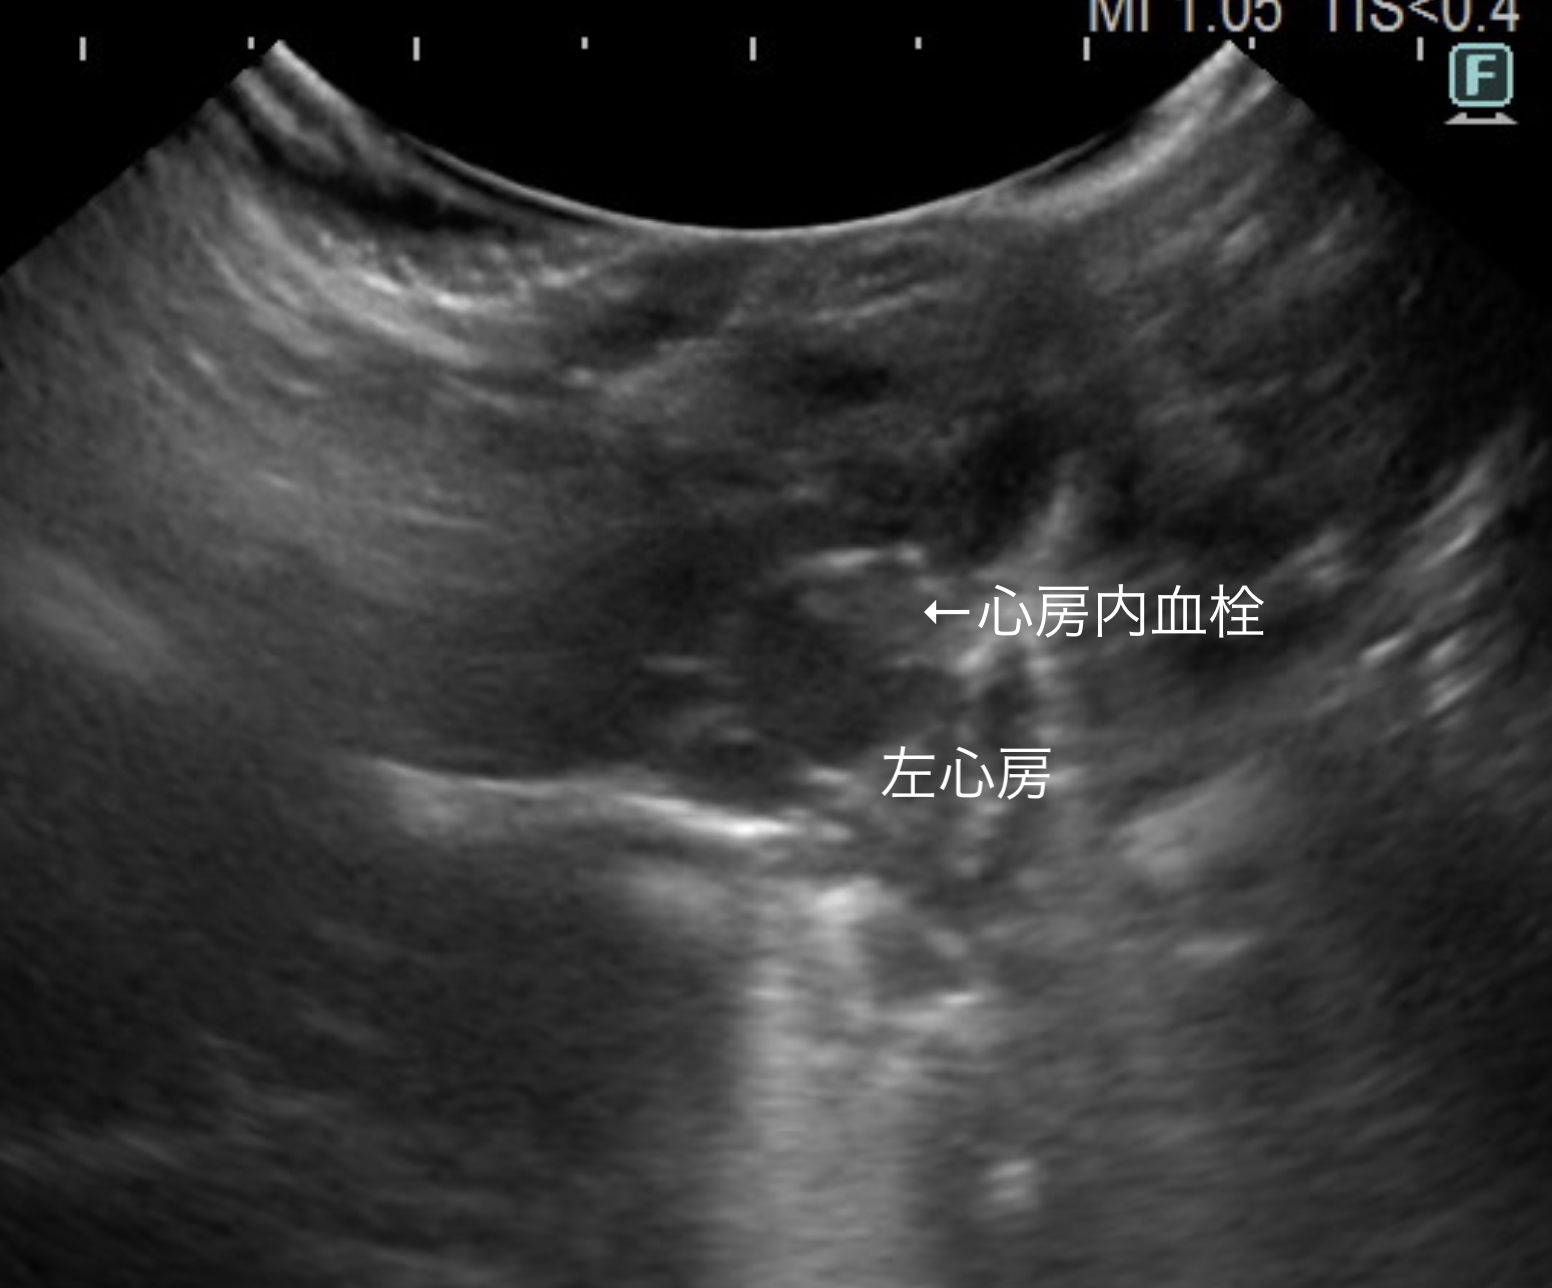

左心房内に血栓(画像)が確認されることも珍しくありません。

画像は拡張型心筋症の1歳8ヶ月ゴールデンハムスターの心エコー画像です。

比較のため同じく正常のゴールデンハムスターのエコー画像と見比べてもらうと一目瞭然で、心臓の内腔が拡張して見えるのがわかるかと思います。